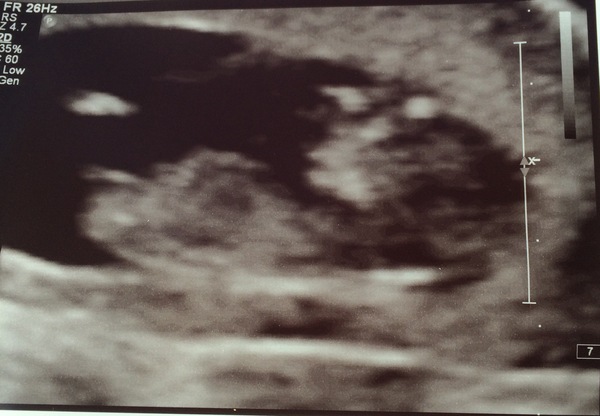

Scan today, what a relief! Measuring exactly 12 weeks so due date stays the same.

April 2017 #4 More baby scans, less morning sickness!

Gorgeous scan! Such a lovely feeling isn't it?!

Gorgeous scan Hayls! Mines Thursday and I'm so scared!!

Had my scan today, also exactly 12 weeks so due date is 17th April. Not long after my own birthday! Have had another migraine though, I'm really starting to strugle to cope with them now, I just want them to stop. But little baby is all healthy